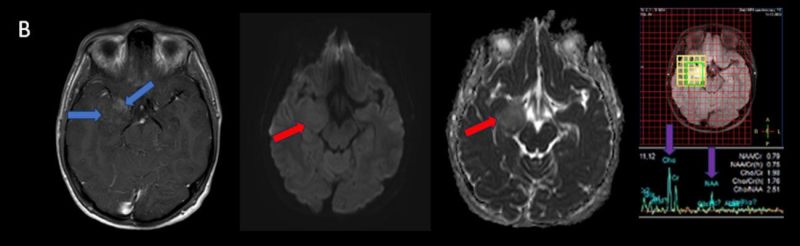

- A) Sağ temporal lob anteromedialinde silik sınırlı BT’de hipodens (ok), MRG’de T2AG ve FLAIR hiperintens (oklar), T1AG izo-hipointens (ok) sinyal özelliğinde ekspansil kitlesel lezyon izlenmektedir.

- B) Lezyon difüzyon görüntüde izo-hiperintens, ADC haritalamada hafif hiperintens izlenmiş olup (oklar) diffüzyon kısıtlılığı göstermemektedir. Lezyonun anterior kesiminde kontrastlı serilerde yamalı kontrast tutulumları (oklar) mevcuttur. MR spektroskopide lezyon düzeyinden elde olunan multivoksel görüntülerde kolin pikinde artış ve NAA da azalma (oklar) dikkati çekmektedir. Kolin/kreatinin oranı 1.76 olarak ölçülmüştür.